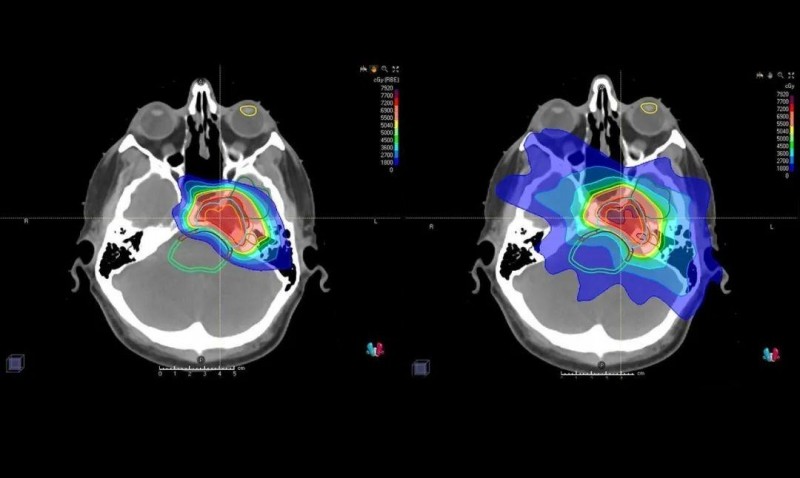

下面是对于同一个患者调强x射线放射治疗(IMRT)平面图(左)和质子治疗计划(右)的对比。颜色渐变程度代表不同辐射剂量,红色高剂量,黄色和绿色中等剂量,蓝色低剂量。

对于这例患者,对比X线放疗,质子计划大幅度减少了肿瘤周围健康组织的辐射剂量,例如右肺、食道和心脏。对这些区域的低剂量将减少辐射诱发的肺炎、吞咽疼痛,还有心脏病危险。

图中患者的脑部扫描显示质子(左)如何专门针对肿瘤,而对周围组织和结构的辐射最小,传统的光子辐射(右)会损坏周围的组织和结构